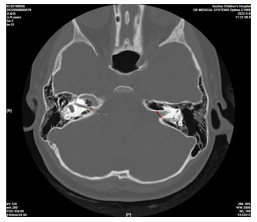

Preoperative HRCT of temporal bone combined with inner ear MRI in patients with cochlear implantation

WU Lin, JIA Huihui, CHEN Mengmeng, GU Wei, WANG Aiping

2026, 24(1): 113-116. doi: 10.16766/j.cnki.issn.1674-4152.004342

32 0

Abstract:

Objective  To address the clinical difficulties of complex anatomical structure and high risk of electrode implantation in children with severe sensorineural deafness during cochlear implantation, and to explore the application value of a combined assessment using high-resolution temporal bone CT (HRCT) and multimodal inner ear MRI before surgery, thereby providing imaging evidence for optimizing surgical planning and reducing the risk of complications.  Methods  A total of 192 children (215 affected ears) with severe or profound sensorineural deafness who underwent surgical CI treatment at the Children' s Hospital Affiliated to Soochow University from January 2021 to December 2024 were selected. All patients underwent temporal bone HRCT and inner ear MRI examinations. The diagnostic efficacy of the two methods for detecting inner ear malformations and abnormal electrode implantation were compared. Univariate and Logistic regression analyses were used to analyze the risk factors associated with abnormal electrode implantation.  Results  Among the 192 cases (215 ears) of children, a total of 140 cases (159 ears) had inner ear developmental malformations, with some unilateral malformed ears presenting with multiple malformations. The detection rate of cochlear malformation identified by inner ear MRI was significantly lower than that by HRCT of the temporal bone (P < 0.05). Transtemporal bone HRCT combined with inner ear MRI examination identified abnormal electrode implantation in 29 ears. Among them, the abnormal implantation rate without inner ear deformity was 5.36% (3/56), which was significantly lower than that in ears with inner ear deformity (16.35%, 26/159, P < 0.05). Logistic multivariate regression analysis showed that increased width of vestibular aqueduct, loss of the labyrinthine segment of the facial nerve canal, greater endolymphatic cyst expansion, elevated intraoperative cerebrospinal fluid pressure level, and older patient age were independent risk factors for abnormal electrode implantation (P < 0.05).  Conclusion  Preoperative temporal bone HRCT combined with inner ear MRI can objectively depict the development and anatomical structure of the inner ear in children. Moreover, the width of vestibular aqueduct, the integrity of the labyrinthine segment of the facial nerve canal, the degree of the endolymphatic sac enlargement, and the intraoperative cerebrospinal fluid pressure are independent risk factors for abnormal electrode implantation.